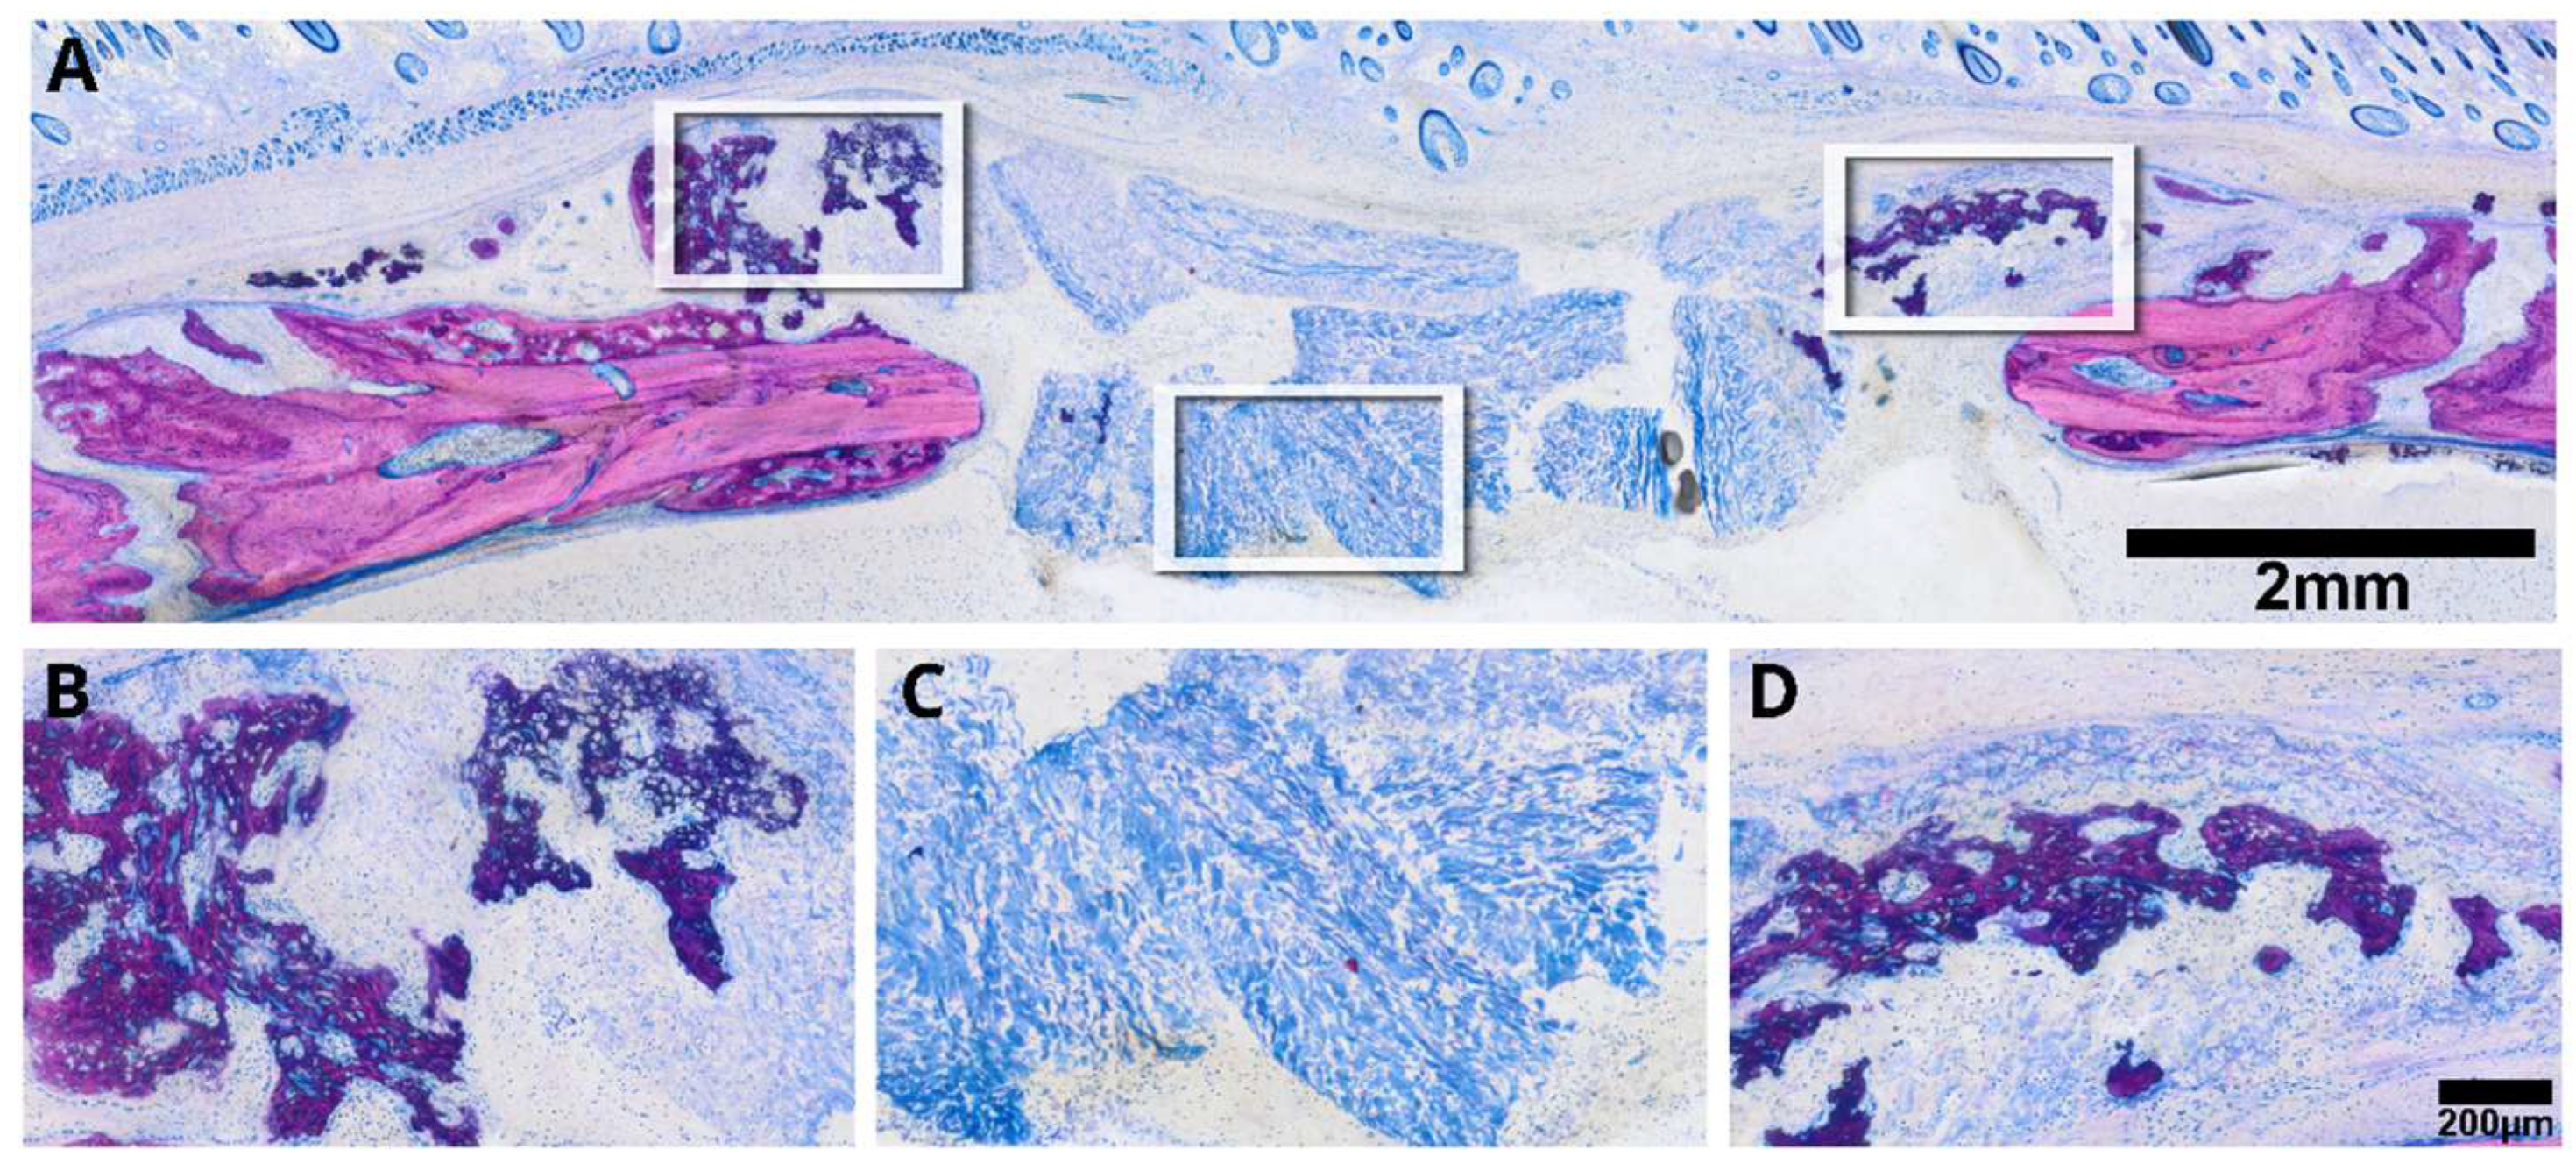

3.3. Minced Collagen Membranes: Histological Analysis